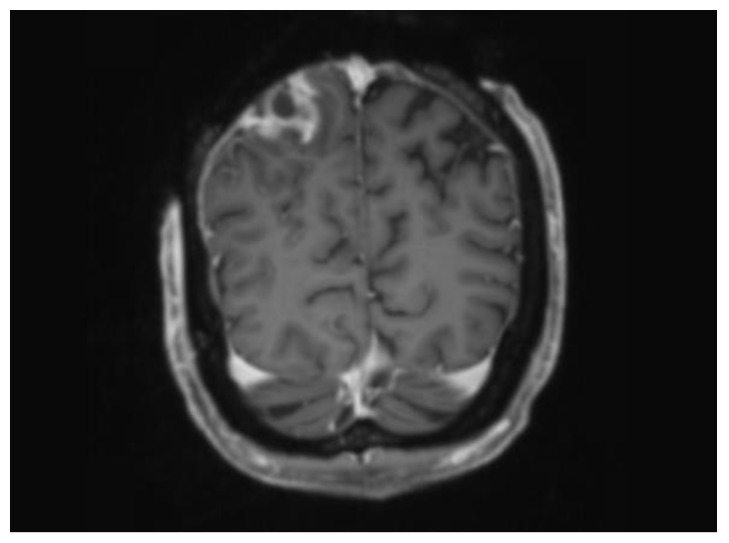

头皮电烧伤有可能造成大面积组织损伤和神经系统并发症。我们介绍了一例患者的病例,他在采摘樱桃时接触到高压电线,导致头皮大面积全厚缺损。入院初期,患者出现进行性全身乏力,入院后一直处于相对静止状态。偶然发现的硬膜外脓肿使他的治疗变得更加复杂,需要紧急手术治疗并进行明确的组织覆盖。使用游离肌皮大腿前外侧皮瓣重建了头皮。术后没有出现并发症。康复治疗后,患者出院回家,功能恢复有限。他可以坐轮椅独立行动,但需要全职护理人员照顾。

Electrical burn injuries to the scalp are at risk of extensive tissue damage and neurological complications. We present the case of a patient who came into contact with a high-voltage power line while cherry picking, resulting in a large full-thickness scalp defect. Early on in his presentation, he developed progressive global weakness which remained relatively static during his admission. An incidental finding of an extradural abscess complicated his management, requiring urgent surgical intervention with definitive tissue coverage. The scalp was reconstructed using a free myocutaneous anterolateral thigh flap. There were no postoperative complications. Following rehabilitation, the patient was discharged home with limited functional recovery. He mobilises independently with a wheelchair and requires full-time carers.